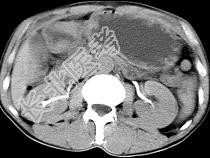

- 单项选择题男,56岁, 无规律上腹痛,左锁骨上淋巴结肿大, 消瘦、乏力,影像检查如图, 最可能的诊断是 ( )

C、胃癌并盆腔种植